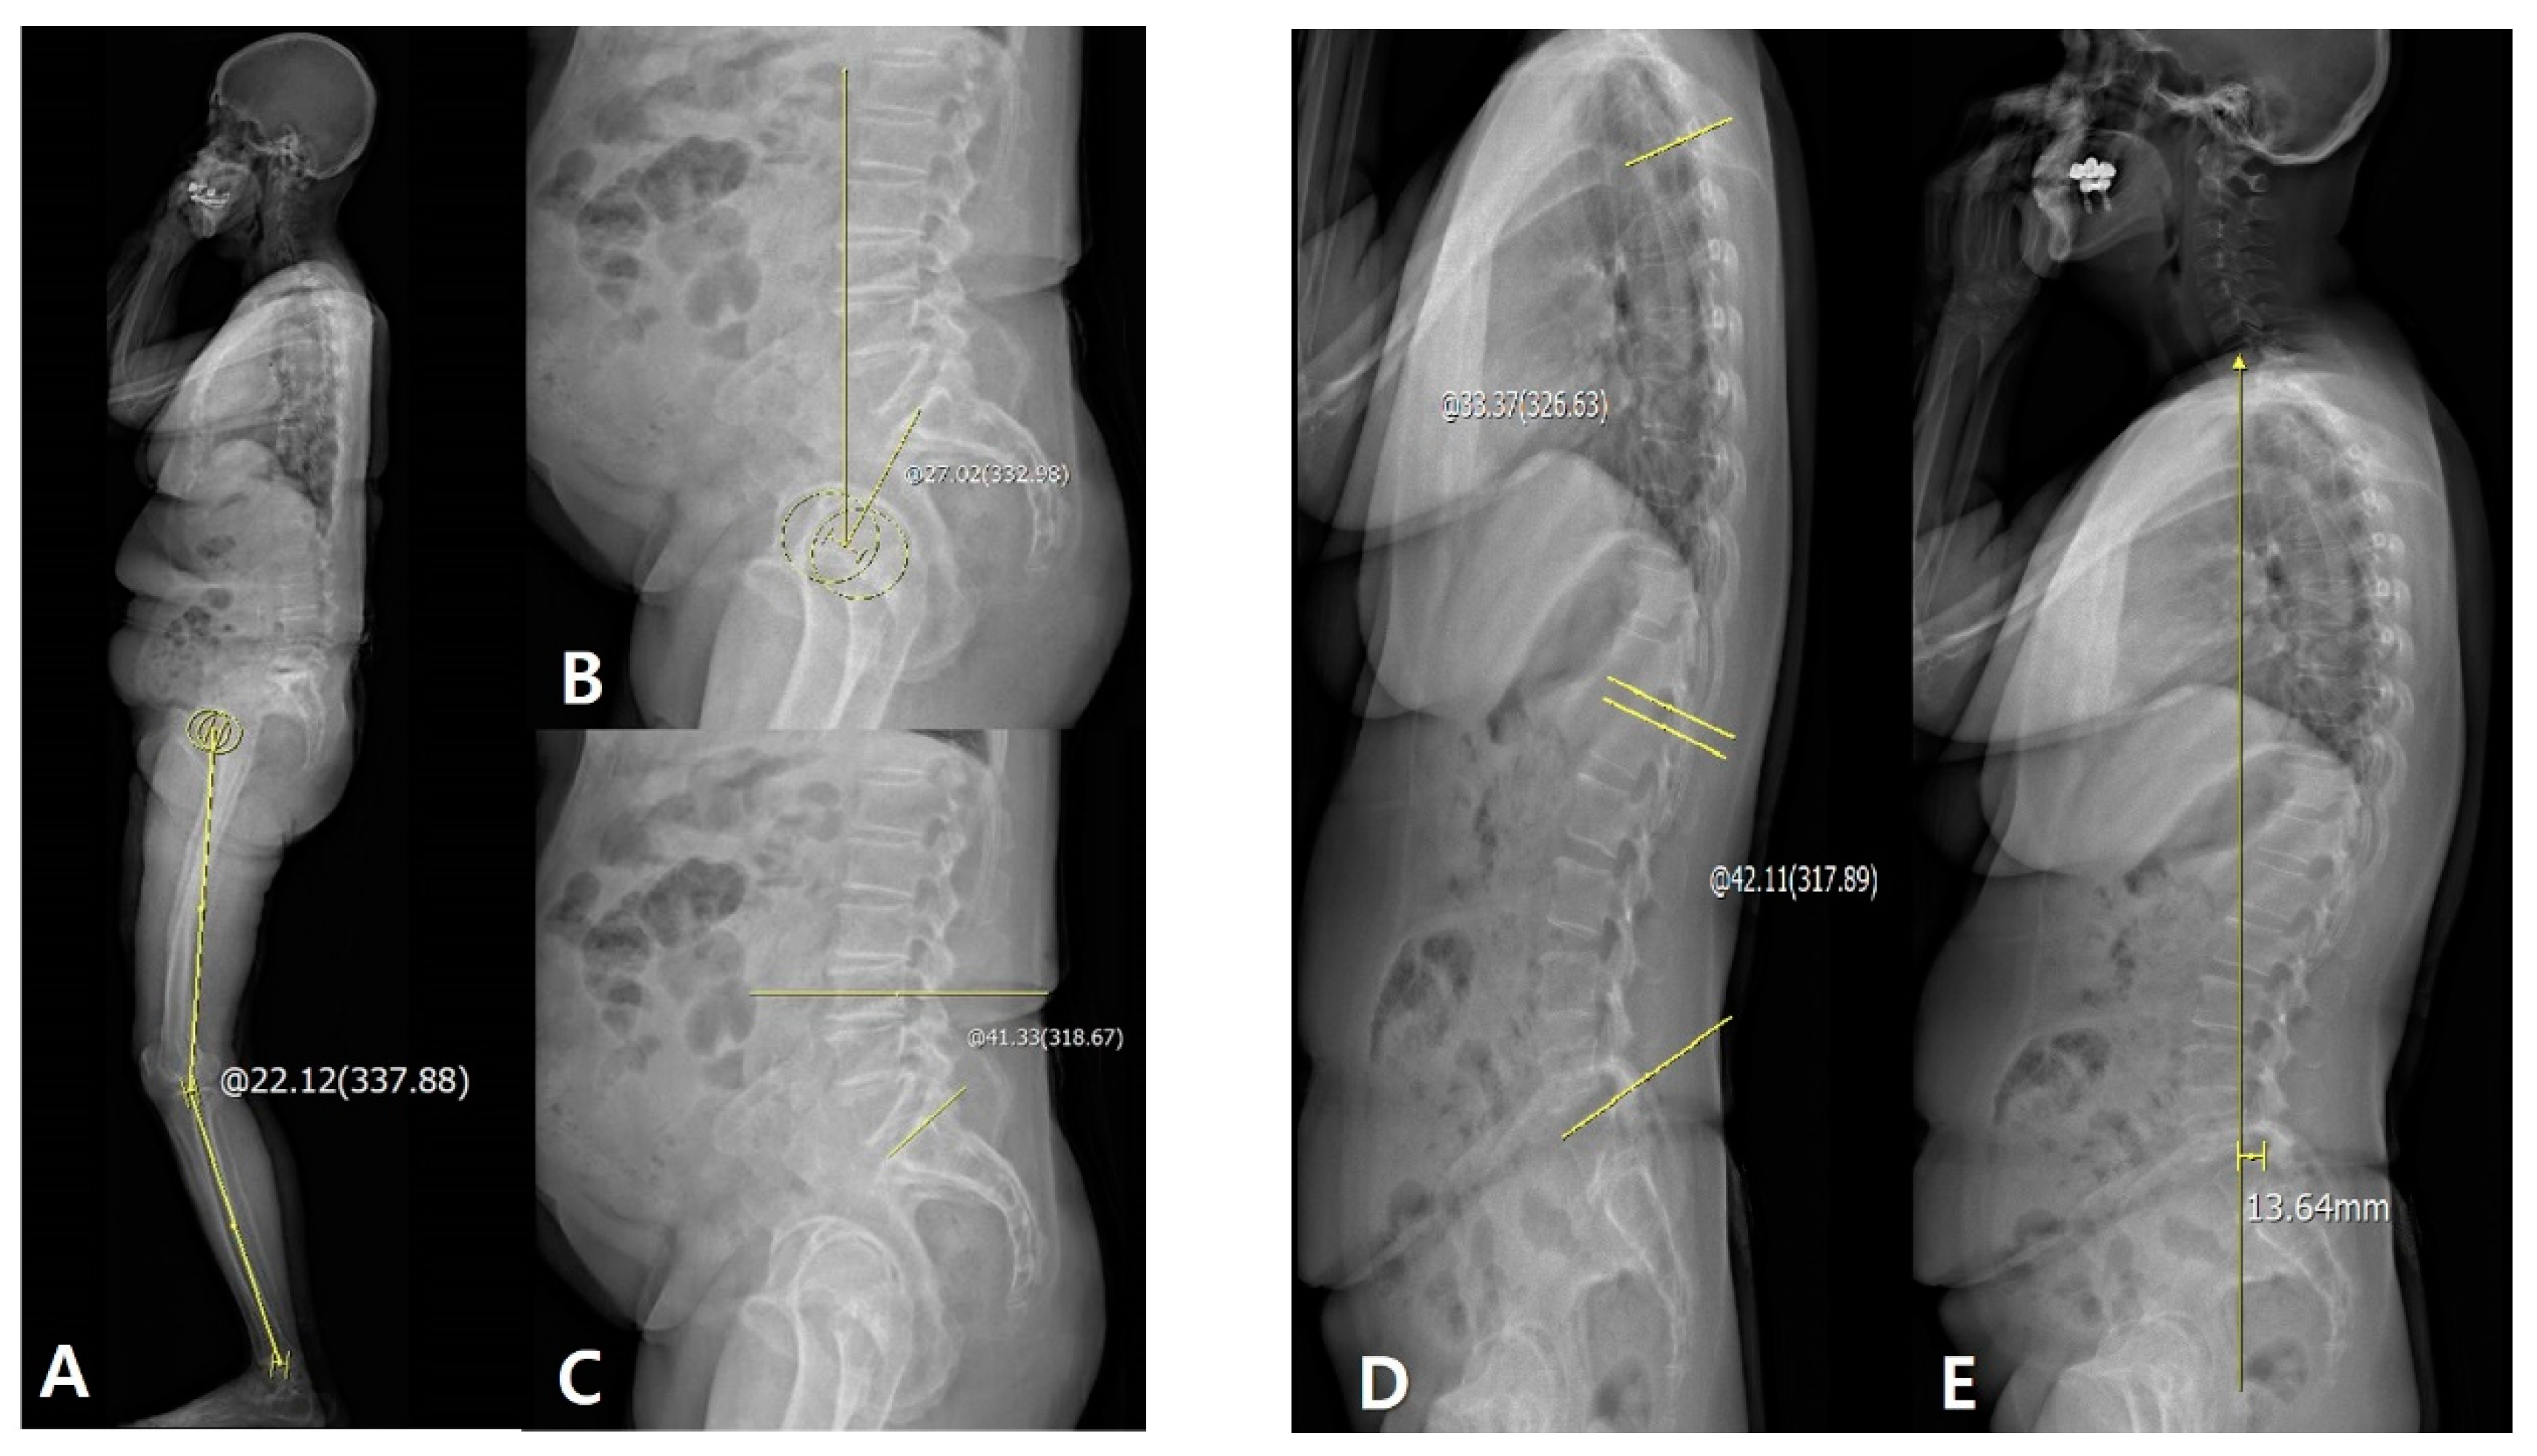

Figure 1. (A) Measurement of hip–knee–ankle (HKA) angle: +22.12°. (B) Measurement of PT: +27.02°. (C) Measurement of SS: +41.33°. (D) Measurement of TK and LL: +33.37° and +42.11°, respectively. (E) Measurement of C7 plumb line-sacrum distance: +13.64 mm. The sagittal HKA angle was defined as the angle between two lines: One joining the center of the femoral head and the center of the knee and the other joining the center of the knee and the center of the superiaor articular surface of the talus.

The sagittal HKA angle was defined as the angle between two lines: One joining the center of the femoral head and the center of the knee and the other joining the center of the knee and the center of the superior articular surface of the talus. The sagittal (HKARt–HKALt) HKARt–Lt angle was defined as the angle connecting the midpoints of each of the centers to the right and left HKAs (Figure 1A). PT was measured as the angle between the line joining the hip axis and the center of the S1 endplate and the reference vertical line (Figure 1B). SS was measured as the angle between the line along the S1 endplate and the reference horizontal line (Figure 1C). LL and TK were measured as the segmental angles of the spinal segments in lordosis (L1–L5) and kyphosis (T4–T12), respectively (Figure 1D). The SVA was measured as the distance between the vertical line from the midpoint of the C7 vertebral body and the posterior corner of S1. If the C7 plumb line was drawn in front of the sacrum, it was recorded as positive (+) (Figure 1E).

LF was measured as the absolute value of the difference between the angles of extension LL (Figure 2A) and flexion LL (Figure 2B). PF was defined as PI that was measured as the angle between the line joining the hip axis and the center of the S1 endplate and the line perpendicular to the S1 endplate (Figure 2C). The difference between the preoperative values and those at postoperative 3 months and 1 year was included in the serial assessments. Delta (Δ) was defined as the difference between the preoperative and postoperative values, and correlations between the lumbosacral flexibility and Δsagittal alignment parameters were evaluated.